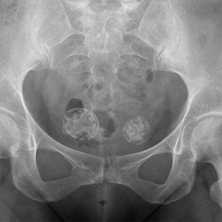

(Слева) Рентгенография в ПЗ проекции, выполненная у пациента с лепрой: разрушение плюсневых костей выражено значительно больше, чем дистальных фаланг. Этот случай не соответствует другим причинам акроостеолизиса, делая лепру наиболее вероятным диагнозом, что и было доказано.

(Справа) Рентгенография в ЗП проекции: выраженный акроостеолизис, большая часть фаланг разрушена. Кроме того, отмечается линейная кальцификация в зоне нерва пальца. Эта комбинация признаков патогномонична для лепры.